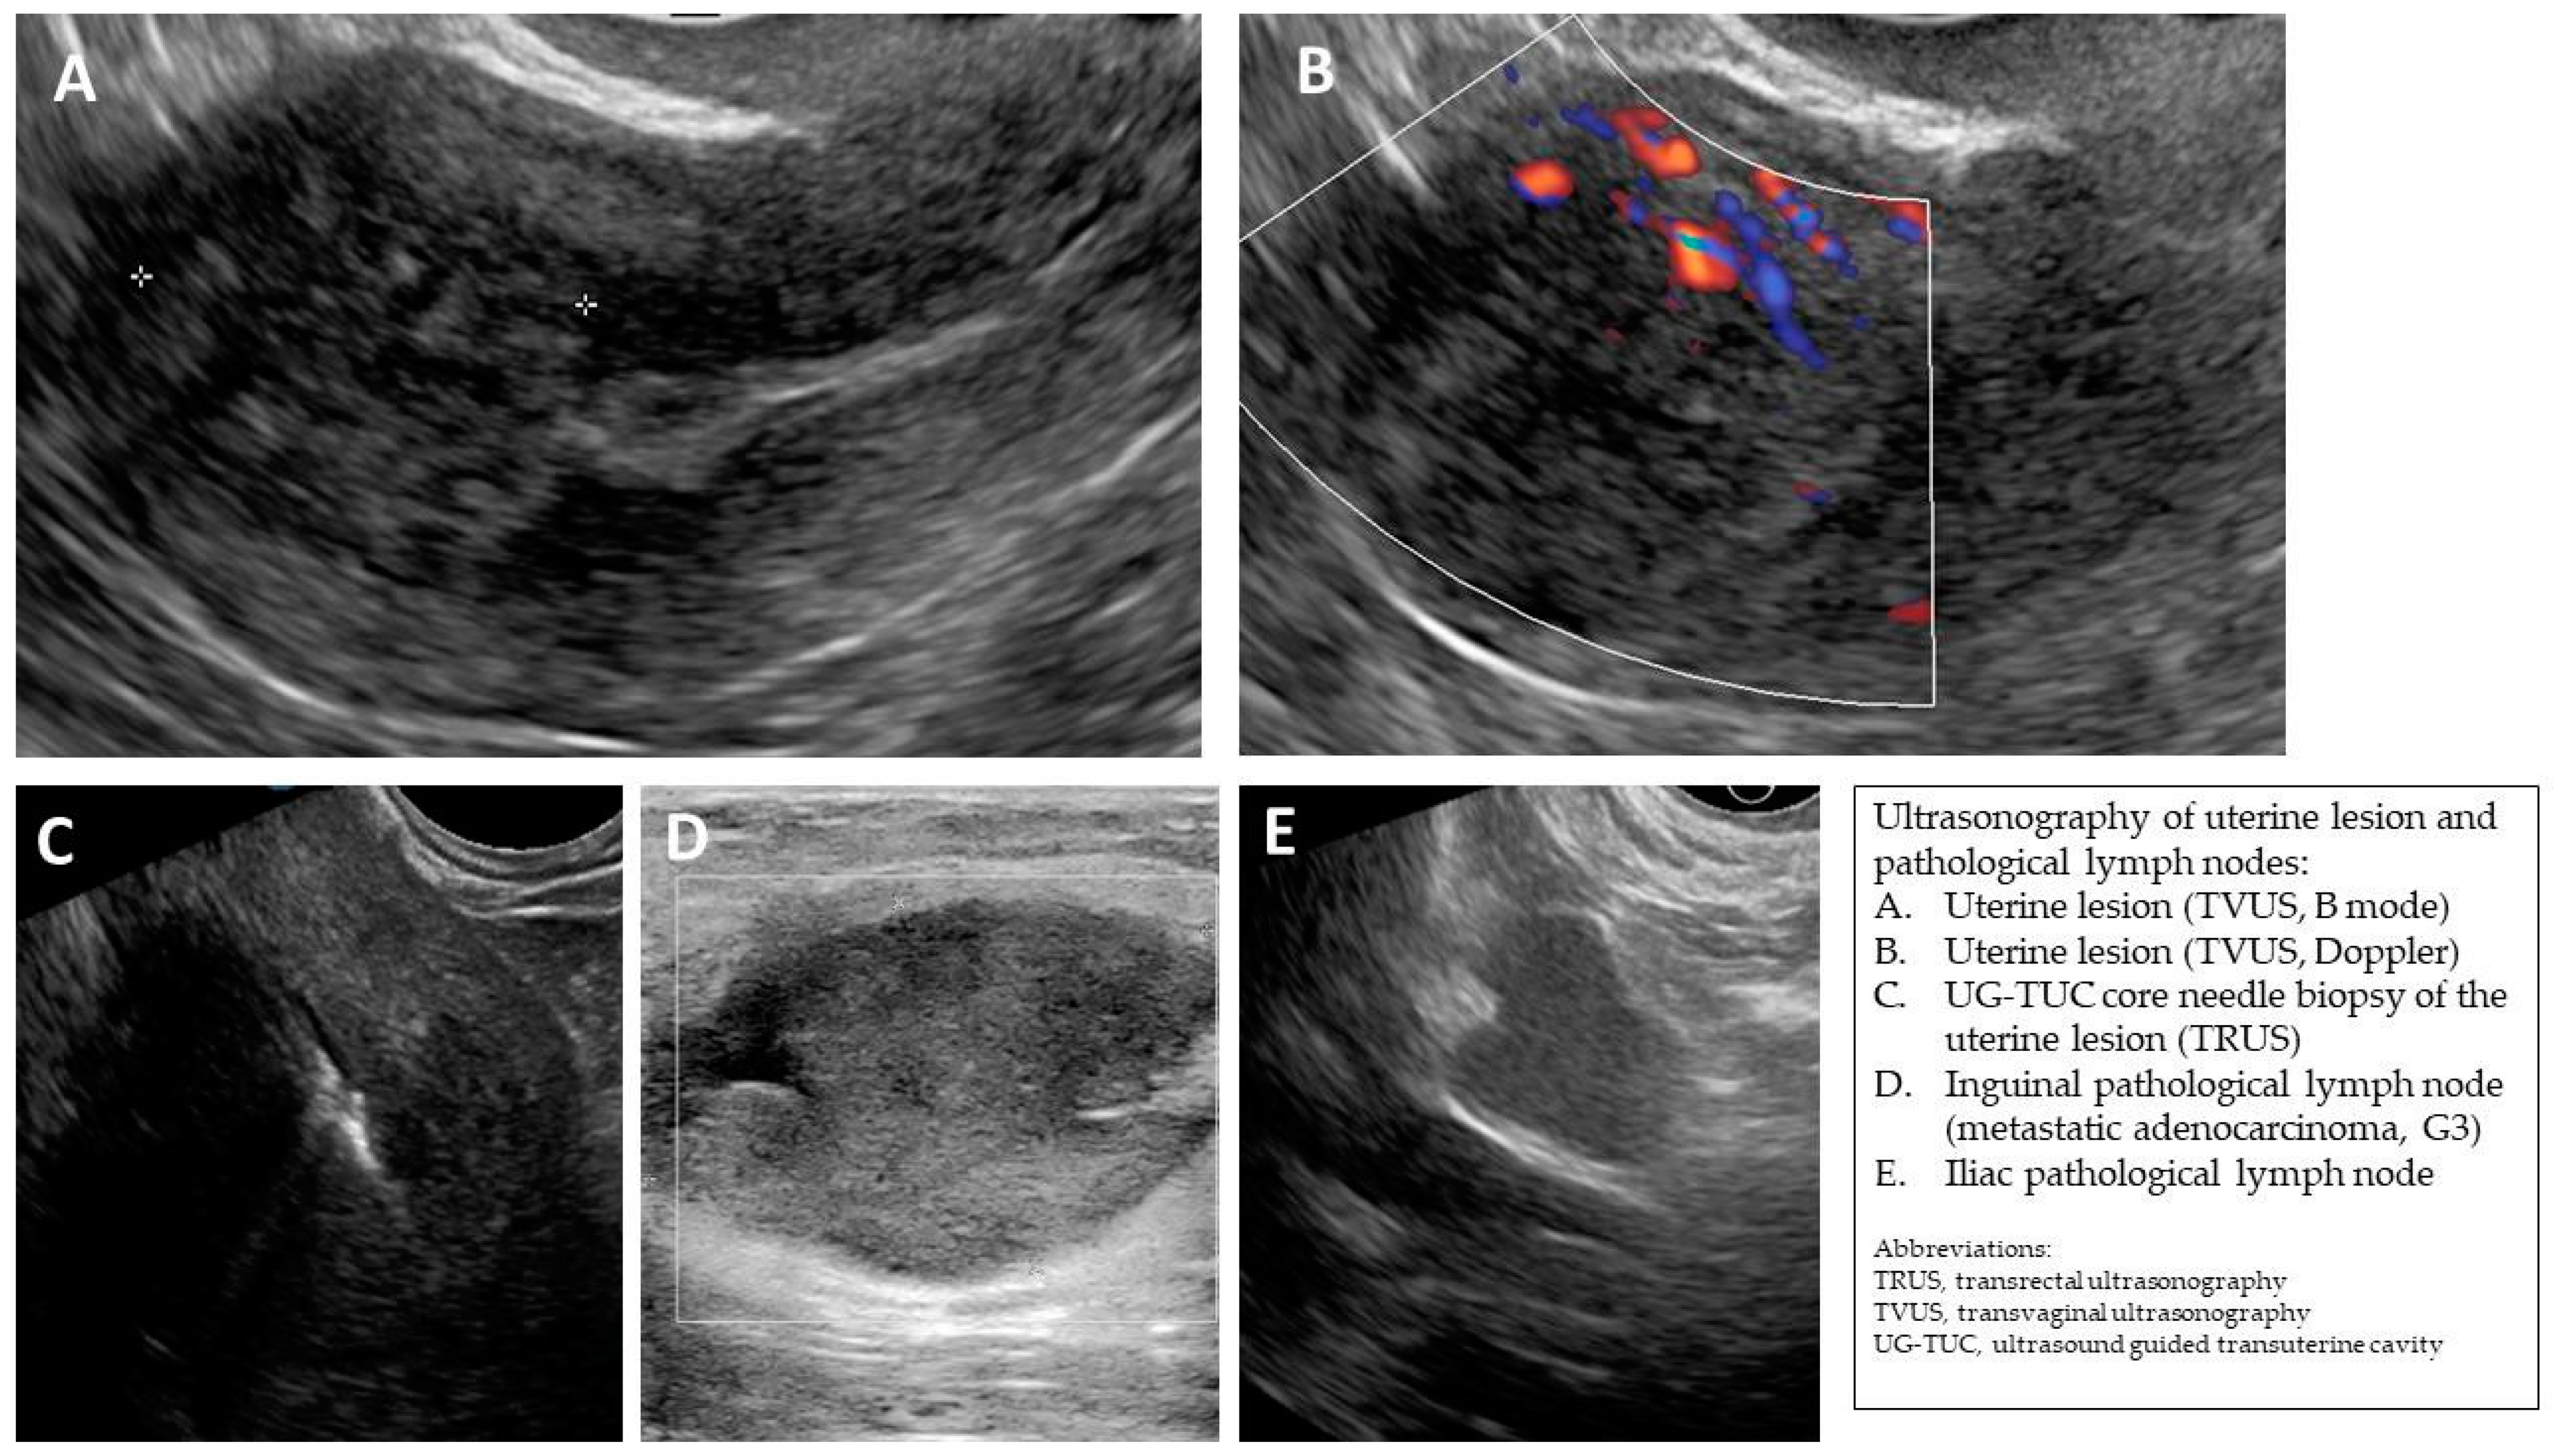

| 1 (44) | Typical uterine lesion (myoma) | Figure A1 | No | Yes | Leiomyoma, cellular variant (UG-TUC core needle biopsy) | Yes (lesion enlarged during follow-up) | Leiomyoma, cellular variant | No | Yes |

| 2 (36) | Sarcoma suspicion | Figure A2 | Yes | Tumorectomy, uterus preservation (young age) | LMS (UG-TUC core needle biopsy) | Yes | LMS | No | Yes |

| 3 (37) | Atypical uterine lesion | Figure A3 | Yes | No | Lipoleiomyoma (UG-TUC core needle biopsy) | No | - | Yes | Yes |

| 4 (56) | Atypical uterine lesion | Figure A4 | Yes | Yes | Leiomyoma (transvaginal ultrasound guided core needle biopsy) | Yes | Leiomyoma and adenomyosis | Yes | No |

| 5 (50) | Atypical uterine lesion (metastatic adenocarcinoma G3 in inguinal lymph node) | Figure A5 | Yes | No | Leiomyoma (UG-TUC core needle biopsy) | No | Uterus / tumor not resected because primary urological carcinoma was diagnosed | Yes | Yes |

| 6 (38) | Atypical uterine lesion | Figure A6 | Yes | No | Leiomyoma, epithelioid variant (UG-TUC core needle biopsy) | Yes (lesion enlarged during follow-up) | Leiomyoma, epithelioid variant | Yes | Yes |

| 7 (29) | Atypical uterine lesion | Figure A7 | Yes | Yes | Leiomyoma (UG-TUC core needle biopsy) | Yes | Leiomyoma with signs of degenerations | Yes | Yes |